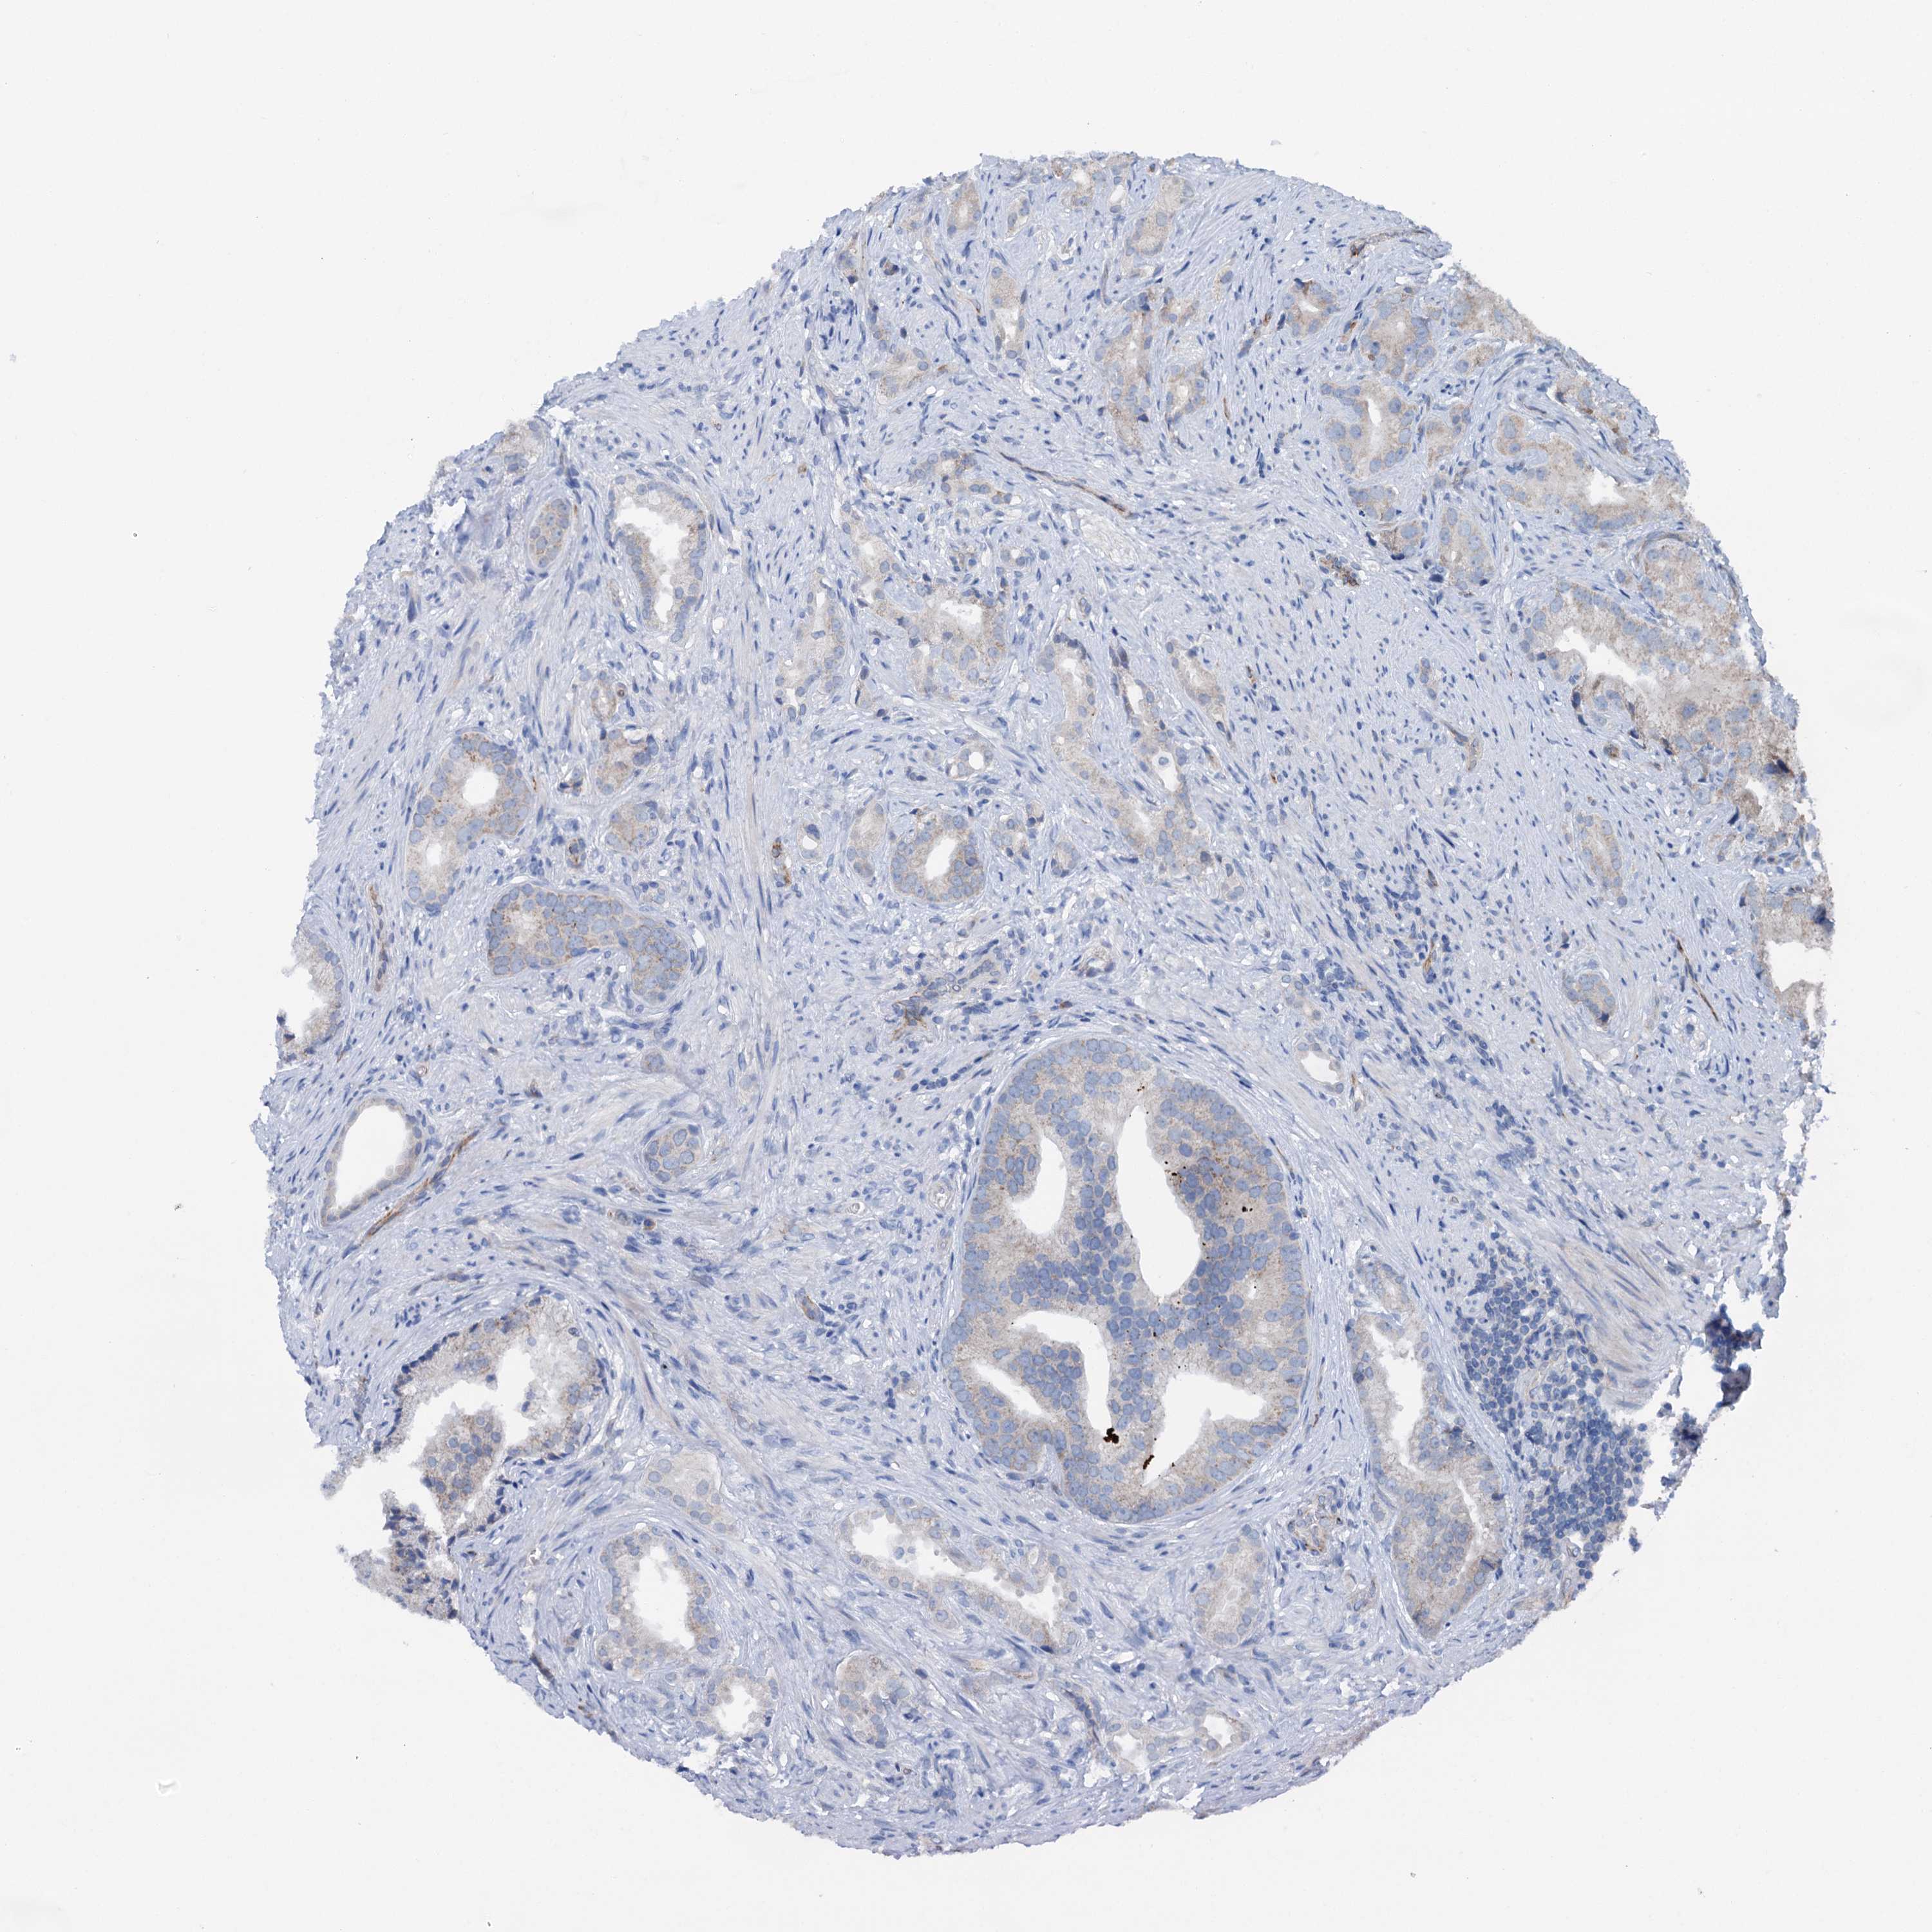

PROSTATE CANCER - Protein expressioni

A mouse-over function shows sample information and annotation data. Click on an image to view it in a full screen mode. Samples can be filtered based on level of antibody staining by selecting one or several of the following categories: high, medium, low and not detected. The assay and annotation is described here.

Note that samples used for immunohistochemistry by the Human Protein Atlas do not correspond to samples in the TCGA dataset.

Antibody stainingi

Antibody staining in the annotated cell types in the current human tissue is reported as not detected, low, medium, or high, based on conventional immunohistochemistry profiling in selected tissues. This score is based on the combination of the staining intensity and fraction of stained cells.

Each image is clickable and will lead to virtual microscopy that enables deeper exploration of all samples and also displays staining intensity scores, fraction scores and subcellular localization as well as patient and tissue information for each sample.

Antibody HPA040867

Staining

High

Medium

Low

Not detected

Intensity

Strong

Moderate

Weak

Negative

Quantity

>75%

75%-25%

<25%

None

Location

Nuclear

Cytoplasmic/membranous

Cytoplasmic/membranous,nuclear

Adenocarcinoma, NOS

Adenocarcinoma, High grade

Adenocarcinoma, Low grade